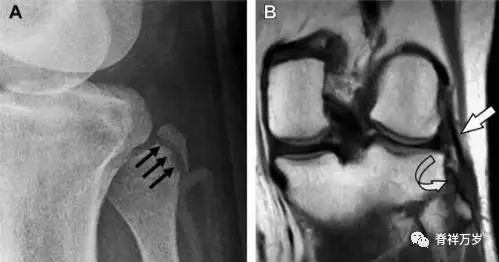

15腓骨头撕脱性骨折

膝关节外侧由髂胫束、股二头肌和肌腱、外侧关节囊韧带及外侧副韧带组成。外侧副韧带对抗过度内旋*力暴**,维持膝关节稳定。当内旋*力暴**足够大时,韧带断裂或腓骨头撕脱性骨折就发生了。在 X 线片上,骨折线垂直于股骨头外侧(图 8)。

图 8 过度伸展引起的腓骨头撕脱性骨折

A 侧位片示腓骨头外侧的垂直骨折(箭头)。B MRI 冠状位 T1 加权像示骨折碎片同时附着于外侧副韧带(箭头)和弓状韧带上(弧形箭头)。